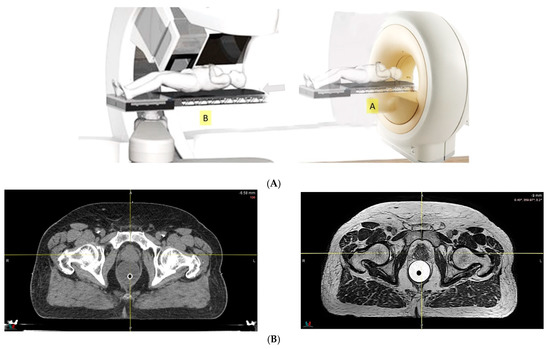

- Because of the inferior soft tissue contrast, orthogonal X-ray imaging systems rely on bony structures for verification of treatment position during patient setup. This type of setup technique can result in large positioning errors due to daily movement of the target and organs at risk (OARs) relative to the bony structures in the former technique. With fiducial markers implanted inside the prostate, many studies concluded that image registration by fiducial markers would reduce matching error. However, some patients may not accept marker implantation. Migration of markers with time may introduce registration errors. Such problems can now be minimized using on-board cone beam CT (CBCT). The better image quality of CBCT can provide 3D images and more information on the anatomic relationships between organs [64,65], which can be used to improve the accuracy of patient setup. Besides patient positioning, CBCT images can also provide information about inter-fractional changes in patient anatomy. In a recent study, an image-based correction method to generate pseudo-CT images from CBCT images was investigated for possible application in proton dose calculations [66] in adaptive PT. MRI, which has the ability to offer fast real-time imaging with high soft tissue contrast in the absence of ionizing radiation exposure [67], is being investigated for use in patient setup in RT. Our study using an external MRI setup room [68] and studies by others [69] indicated that patient positioning accuracy on the order of 1 mm is feasible, and is a significant reduction from that of conventional setup systems.